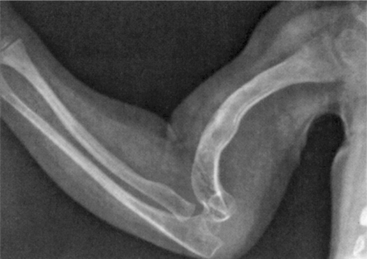

This disease has a wide range of clinical presentations ranging from a normal appearance with occasional fractures to severe involvement with growth retardation and long bone and spinal deformities (Fig. 23-30; see Table 23-9). In its severe forms, OI is evident at birth because of the fractures and deformity that have occurred in utero.

Figure 23-30 Child with osteogenesis imperfecta type III. This shows defect of all four limbs and increased anteroposterior diameter of the chest. Note the spinal deformity. (From Bullough PG: Bullough and Vigorita’s orthopaedic pathology, ed 3, St Louis, 1997, Mosby, p 133.)

Diagnosis of OI is based on clinical manifestations and skin biopsy that looks at collagen. The collagen defect is used to determine what type of OI the person has according to the Sillence classification. Bone scans and x-ray films show evidence of multiple old fractures and skeletal deformities. Skull radiographs show wide sutures with small, irregularly shaped islands of bone called wormian bones.

Fracture immobilization is as minimal as possible to prevent disuse atrophy. A repeated cycle of fractures-immobilization of the same bone can inhibit progress in mobility and the development of strength (Fig. 23-31). The use of intramedullary rods is one way of managing recurring fractures (Fig. 23-32). Indications for this procedure include more than two fractures in the same long bone within a 6-month period, lower extremity bone angles greater than 40 degrees, or very unstable lower extremities in a child who appears ready to walk. Telescoping intramedullary rods are used to stabilize the bones, elongating as the bone grows, although this procedure is not without risk.

Figure 23-31 Radiograph of upper extremity in a person with osteogenesis imperfecta. This radiograph shows severe osteoporosis, slender bones, and multiple healed fractures. (From Bullough PG: Bullough and Vigorita’s orthopaedic pathology, ed 3, St Louis, 1997, Mosby, p 134.)